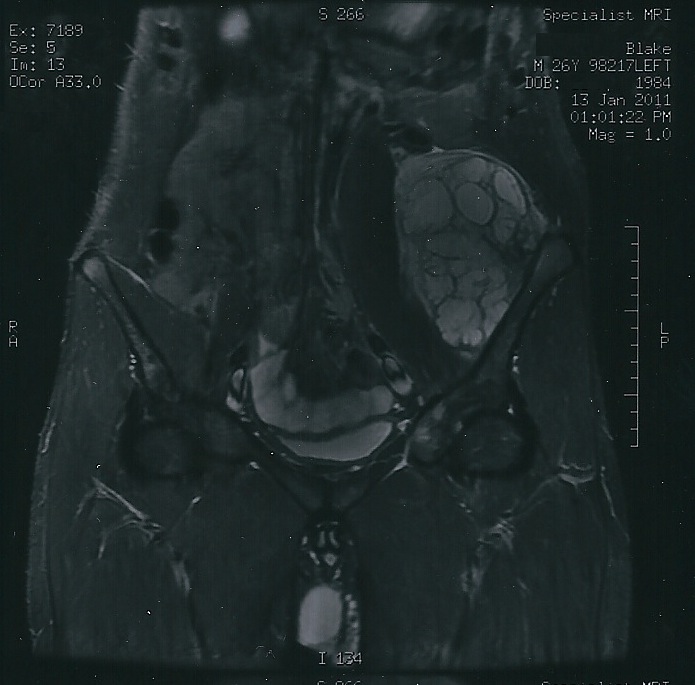

🧲 Resonancia magnética (RM)

La RM es la prueba de elección para valorar la extensión medular, la masa de partes blandas y la planificación quirúrgica.

Figura 3. RM de condrosarcoma para valorar la extensión local.